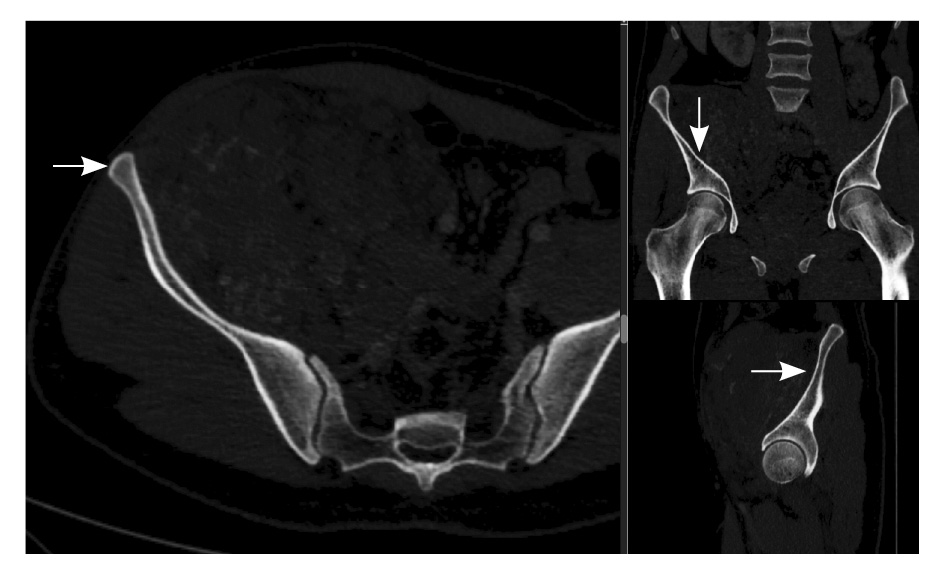

Рис. 2. Мультиспиральная компьютерная томография органов брюшной полости и забрюшинного пространства, режим костного окна. Кортикальный слой правой подвздошной кости прослеживается равномерно на всем протяжении, без признаков деструкции (стрелки)